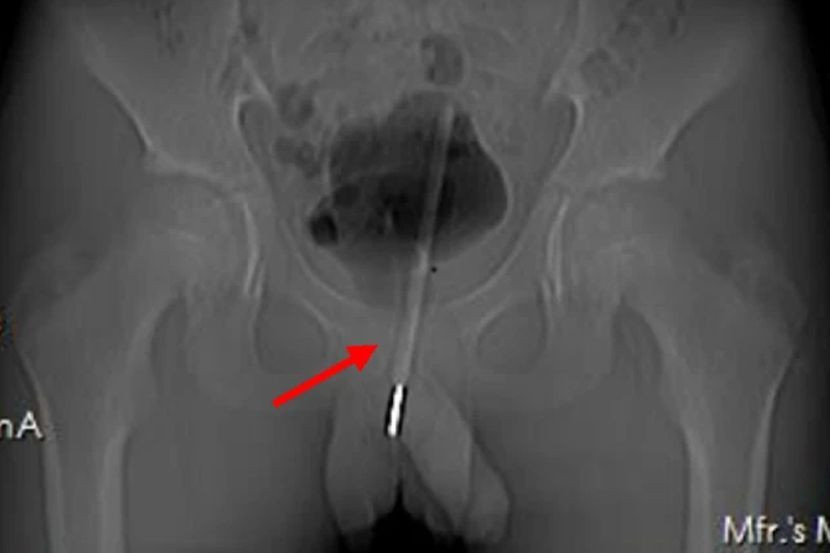

Imbasan X-Ray menunjukkan termometer itu berada jauh di atas saluran kencing sehingga memasuki pundi kencing kanak-kanak malang itu.